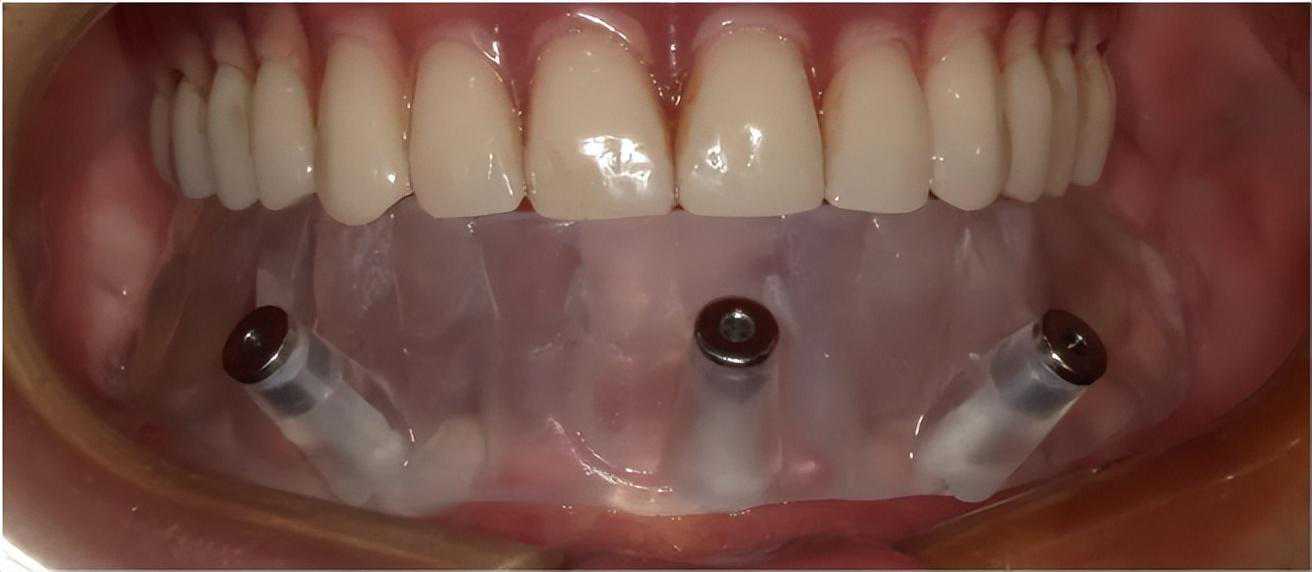

黑格为周先生3D打印的种植导板在口内固位

植体植入后,医生为周先生打印第一副临时牙。周先生上午去种牙,下午就戴上临时牙回家了,晚上还用临时牙吃上了香喷喷的卤面。

种完牙,结果后悔了……为了让周先生有更好的使用体验,一周后医生根据数字模型,又给他制作了第二副临时牙。

随后,医生根据周先生的两次临时牙的试戴体验,为他逐步微调,3D打印出颜色更自然,外观更精致,强度、耐磨度更高的终修复牙。

经过3个月调试修改,3D打印出周先生的终修复牙

2022年1月,周先生戴上了下颌的终修复牙,上个月,他又完成了上颌的数字化种植,至此,他的种植之路圆满结束。